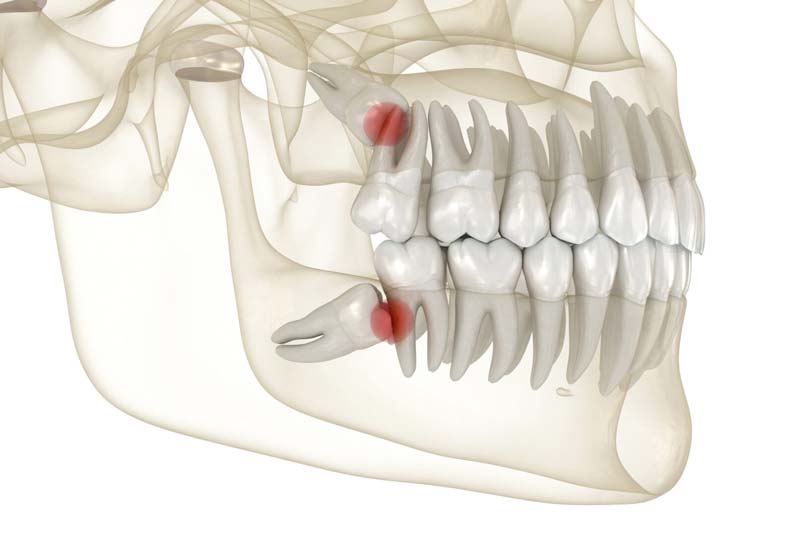

سیاری از افراد در جستجوی بهترین خدمات جراحی دندان عقل در الهیه تهران و به دنبال کلینیک هایی با تخصص و تجربه بالا هستند. جراحی دندان عقل در این منطقه در تهران به دلایل مختلفی ضروری است، چرا که دندان های عقل معمولاً در سنین جوانی رشد میکنند و ممکن است با مشکلاتی مانند درد، عفونت، و آسیب به دندانهای مجاور همراه شوند. این مشکلات میتوانند به عواقب جدیتری مانند ایجاد کیست و تومور منجر شوند.

| وجود کیست یا تومور | تشکیل کیست یا تومور در اطراف دندان عقل که نیاز به جراحی دارد تا از آسیب به بافتهای اطراف جلوگیری شود. |

دندان عقل نهفته که به درستی رشد نمیکند: دندان عقل که در زیر لثه یا استخوان باقی میماند و نمی تواند به درستی بیرون بیاید، به عنوان دندان نهفته شناخته میشود. این وضعیت معمولاً نیاز به جراحی برای جلوگیری از عوارض بیشتر دارد.